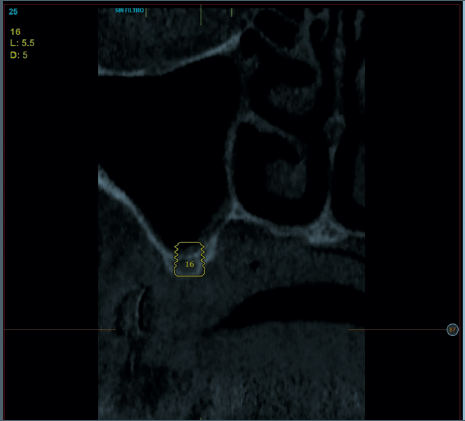

La fluorosis dental es una condición irreversible originada durante el desarrollo dental que genera pigmentaciones intrínsecas, alteraciones en el esmalte manifestadas a manera de manchas blancas, amarillas o marrones, que perjudican la estética y repercuten en el desenvolvimiento social. El presente reporte de caso clínico describe la combinación de los procedimientos de microabrasión y blanqueamiento dental, como alternativas en la eliminación de pigmentaciones dentales. Después del diagnóstico de la patología, verificación de ausencia de lesiones pulpares y caries, una explicación minuciosa a la paciente y obtención del consentimiento informado, se realizó limpieza de las superficies dentales y, bajo aislamiento absoluto, se procedió a realizar la técnica de microabrasión mediante ácido clorhídrico al 6,6% siguiendo las instrucciones del fabricante. Concluido el procedimiento y, observando que era posible mejorar aún más la estética, se decidió ejecutar el procedimiento de blanqueamiento dental, a base de peróxido de hidrógeno al 40% en el consultorio, seguido por peróxido de carbamida al 10% aplicado en el domicilio. Al finalizar el tratamiento se observó uniformidad en el color dental, conjugados con una evidente mejora en la calidad de vida y relación social de la paciente.